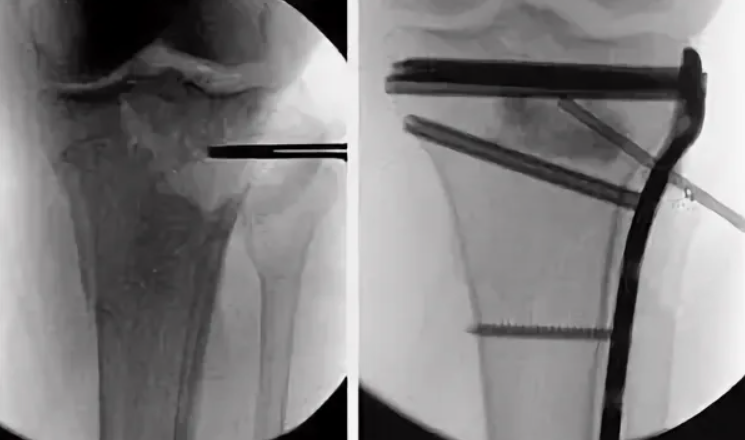

Пациент 52 лет поступил с диагнозом «закрытый многооскольчатый внутрисуставной перелом дистального метаэпифиза левой ББК со смещением отломков». Травма получена в результате падения с высоты четыре метра на прямые ноги. Через шесть часов после поступления в стационар осуществили фиксацию левой голени и стопы аппаратом наружной фиксации, после чего выполнили компьютерную томографию, на основании которой изготовили полноразмерный 3D-прототип (рис. 2).

Произвели разметку суставной поверхности прототипа (рис. 3) и определили ключевые фрагменты, — задне-латеральный и передне-латеральный, точки выхода перелома — в передне-центральном и задне-медиальном квадратах. На основании полученных данных выбрали хирургические доступы: заднемедиальный и передне-латеральный. Осуществлён остеосинтез из этих доступов с установкой передне-латеральной пластины и 1/3 трубчатой пластины сзади (рис. 4). Задне-медиальный доступ позволил полностью визуализи ровать перелом заднего края ББК, осуществить репозицию отломков ad occulus и уложить ранее пре моделированную при помощи 3D-прототипа 1/3 трубчатую пластину. Далее пациента перевернули на спину, выполнили передне-латеральный доступ. Метадиафизарный компонент перелома фикси ровали передне-латеральной премоделированной L-образной пластиной, передне-латеральный фраг мент (Chaput) — винтом. Применённый доступ позволил визуализировать передней край вырезки малоберцовой кости для прецизионной репозиции фрагмента Chaput. Послеоперационный период протекал без осложнений, раны зажили первичным натяжением. Больной разрабатывал движения в оперированном голеностопном суставе в течение восьми недель.

По шкале AOFAS AHS сумма баллов составила 82 балла, по шкале VAS-FA — 41 балл, в обоих случаях сумма баллов соответствовала отличным результатам. При оценке рентгенограмм (рис. 5) по критериям mRUST получено 13 баллов, что соответствует перелому в стадии консолидации. Миграции фикса торов, вторичного смещения не выявлено.